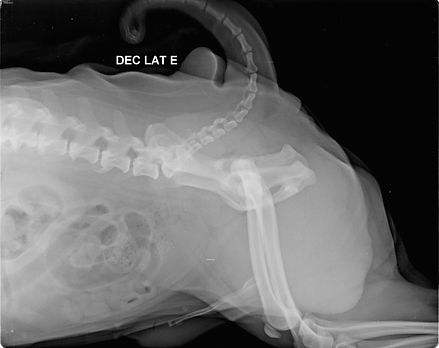

Cão da raça PUG, 2 anos de idade, 11 kg, imagens ombro direito (ML, CaCr) e pelve (LL, VD). Exuberantes osteófitos periarticulares e acentuado arrasamento acetabular, incongruência articular, com moderado remodelamento de cabeças femorais e espessamento de colos femorais. Agenesia do sesamóide gastrocnêmico medial direito.

Moderada esclerose e irregularidade das superfícies articulares do cotovelo esquerdo, com reação óssea remodelada grandes projeções ósseas em processos ancôneos e área supra-epicondilar de úmero, além de remodelamento de cabeças radiais, grandes osteófitos peri-articulares, entesófito projetando-se caudalmente aos epicôndilo umeral medial e maiores nas margens laterais e mediais de epicôndilo umeral.

Conclusões: avançadas alterações artrósicas secundárias à severa displasia coxofemoral bilateral e grave displasia do cotovelo.